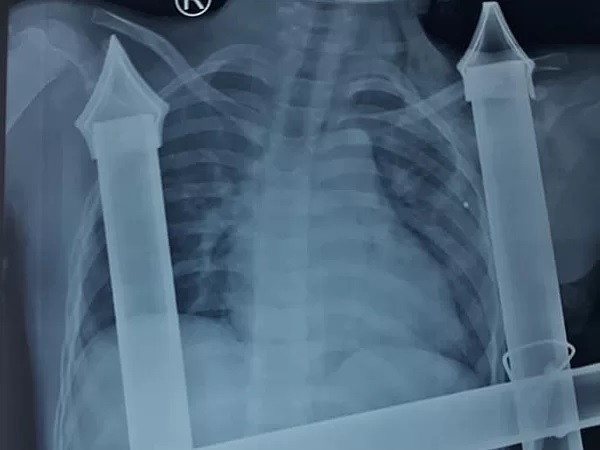

Phim chụp X-quang cho thấy thanh sắt đâm xuyên dọc thành ngực trái bệnh nhi - Ảnh: Vnexpress. |

Bệnh nhi T.A.D nhập viện cùng với hẳn 1 đoạn hàng rào sắt còn dính chặt trên cơ thể, phần cọc sắt dài hơn 10 cm xuyên dọc thành ngực trái, chảy máu nhiều.

Theo Vnexpress, các bác sĩ phẫu thuật cố gắng tháo đầu sắt nhọn và xử lý các tổn thương mạch máu lớn đang làm chảy máu ồ ạt, đe dọa tính mạng của bệnh nhi ngay trên bàn mổ. Bé bị đứt cơ ngực lớn, cọc sắt hàng rào tạo nên đường hầm trong khoang ngực kéo dài trên 10 cm. Các bác sĩ đã phải truyền máu, thực hiện mổ khẩn cấp để giữ sinh mạng bệnh nhân.